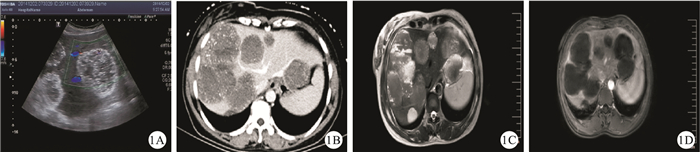

一般情況下應用超聲、CT和MRI 3種方法結合臨床表現與實驗室檢查肝海綿狀血管瘤即可明確診斷[7]。但在臨床實際工作中,由于肝海綿狀血管瘤的影像學表現不典型,誤診現象時有發生[8],主要存在兩種情況:一種情況是將肝海綿狀血管瘤誤診為其他肝臟腫瘤如肝膽管細胞癌、肝細胞癌或轉移性肝癌等[8-9],尤其是合并肝硬化與慢性肝病背景的患者更易將其海綿狀血管瘤誤診為肝細胞癌,多發血管瘤尤其是小血管瘤則易誤診為轉移性肝癌。筆者曾遇一慢性乙型肝炎的42歲女性患者,其肝多發巨大占位,經多家醫院B超、增強CT、MRI、PET-CT檢查,甚至做了超聲引導下肝穿刺活檢亦未能確診,不能除外轉移癌,患者與家屬不得已放棄治療(圖 1),但6年后病情未見明顯加重,故對既往診斷產生質疑,最后手術探查證實為肝海綿狀血管瘤。有文獻[10]報道,肝左外葉的血管瘤因壓迫胃壁,行胃鏡與增強CT檢查均誤診為胃間質瘤,最后行開腹手術方獲診斷。此類誤診,容易使患者產生不必要的恐慌與精神壓力,易步入過度治療的陷阱。另一種情況是將其他肝臟腫瘤誤診為血管瘤如血運豐富的小肝癌,小的肝內膽管細胞癌或轉移性肝癌,少見的肝臟肉瘤如軟骨肉瘤等很容易誤診為血管瘤[11]。該類誤診則易使患者放松警惕,耽誤惡性腫瘤的早期治療,產生嚴重后果,應盡力避免。